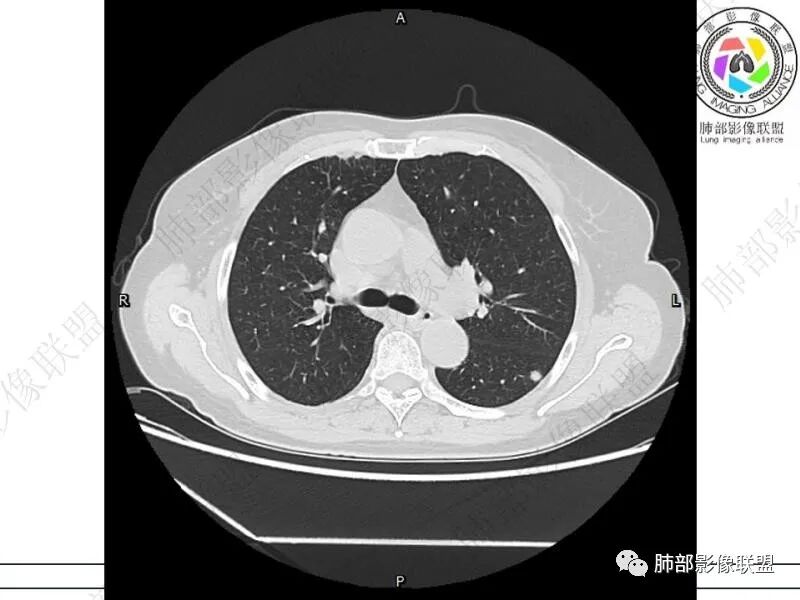

丽:双肺下叶胸膜下多发片状高密度影,边缘模糊不清,内可见支气管穿行,病变长轴平行于胸膜,考虑感染性病变,隐球菌

媛:肠癌术后,免疫力低下。两肺胸膜下结节及实变影,实变影长轴平行于胸膜,密度均匀,边界偏清,周围有晕征,短期复查进展,虽隐球菌荚膜抗原检测阴性,还是考虑隐球菌,鉴别OP

谢加平:结肠癌术后史,两肺胸膜下多发结节及斑块实变病灶,实边边界平直征(亚急性和慢性病变过程),双肺下叶后基底段胸膜下为甚,与胸膜平行特点,见支气管充气征,边缘模糊的GG0,首诊2022年11月18日肺部CT,与治疗11月28日对比,病灶未吸收,双肺下叶胸膜下病灶有侧向融合特点,综合分析符合炎性肉芽肿,隐球菌感染。

良孑:两肺胸膜下多发相类似结节,部分结节有晕及晕中软毛刺,部分结节侧向融合,长轴与胸膜平行,结节边缘可见刀切征,右半结肠癌术后免疫力低下,综合考虑支持隐球菌

老年女性,结肠癌术后。两下肺胸膜下为主片状实变,右下肺短期复查融合且病灶长轴平行于胸膜,实变内可见支气管充气征,边缘磨玻璃晕,另两肺内胸膜下散在数枚小结节状、楔形实性灶。考虑感染性病变,隐球菌可能,鉴别肺转移。

2.影像特征:双肺胸膜下多发实性结节、磨玻璃影及实变影,胸膜下优势分布、晕征、胸膜下脂肪间隙存在,部分病灶边界平直征,有侧向融合趋势。